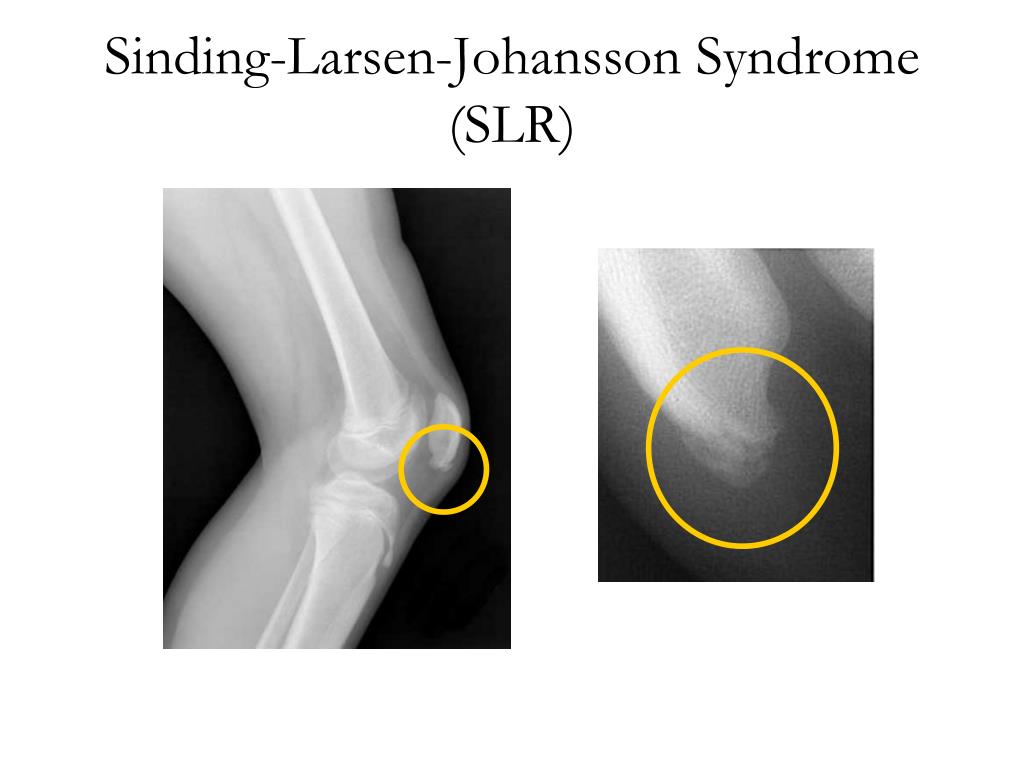

Ларсена йохансона

Ларсена йохансона 146 фото